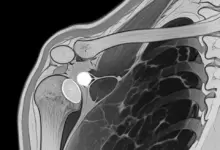

A capsulite adesiva é caracterizada por inflamação da cápsula articular do ombro, seguida por espessamento e rigidez progressiva.

Capsulite adesiva pode parecer bursite, tendinite do manguito rotador ou até lesões do labrum, já que todas provocam dor no ombro.

O diagnóstico começa com história clínica e exame físico, observando padrões de limitação e dor em testes específicos.

Exames de imagem entram como complemento.

- Radiografias ajudam a excluir artrose e alterações ósseas.

- Ultrassom e ressonância podem ser úteis para avaliar estruturas como tendões e bursa, principalmente quando existe suspeita de problemas associados.